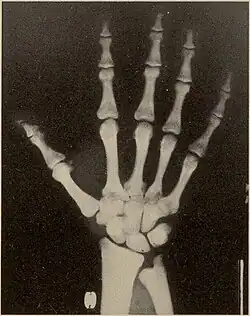

Pycnodysostosis causes the bones to be abnormally dense; the last bones of the fingers (the distal phalanges) to be unusually short; and delays the normal closure of the connections (sutures) of the skull bones in infancy, so that the "soft spot" (fontanelle) on top of the head remains widely open.[9] Because of the bone denseness, those with the syndrome suffer from fractures.[7]

Other abnormalities involve the head and face, teeth, collar bones, skin, and nails. The front and back of the head are prominent. Within the open sutures of the skull, there may be many small bones (called wormian bones). The midface is less full than usual. The nose is prominent. The jaw can be small. The palate is narrow and grooved. There will be delay in fall of milk teeth. The permanent teeth can also be slow to appear. The permanent teeth are commonly irregular and teeth may be missing (hypodontia). The collar bones are often underdeveloped and malformed. The nails are flat, grooved, and dysplastic. High bone density, acro-osteolysis and obtuse mandibular angle are the characteristic radiological findings of this disorder.[10]

- Hypoplasia or aplasia of the distal phalanges and ribs